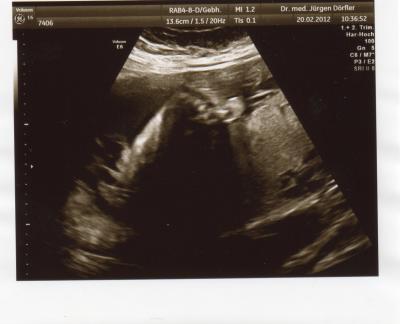

Huhu,hatte heute wieder termin zur VU,es ist alles ok Gewicht ca.1300g Größe ca.38cm Und hänge noch ein bildchen dran von dem kleinen Füsschen Nun mus ich alle 14tage zur VU LG und ein schönen sonnigen tag

Bild zu Zurück vom FA - Forum für Mai - Mamis

-lichen Glückwunsch!!! So ein Bild vom kleinen Füßchen bringt mich echt zum schmelzen!!! ZUCKERSÜß!!!!

Toll, das alles ok ist und das Bild mit dem Füßchen ist echt süß!